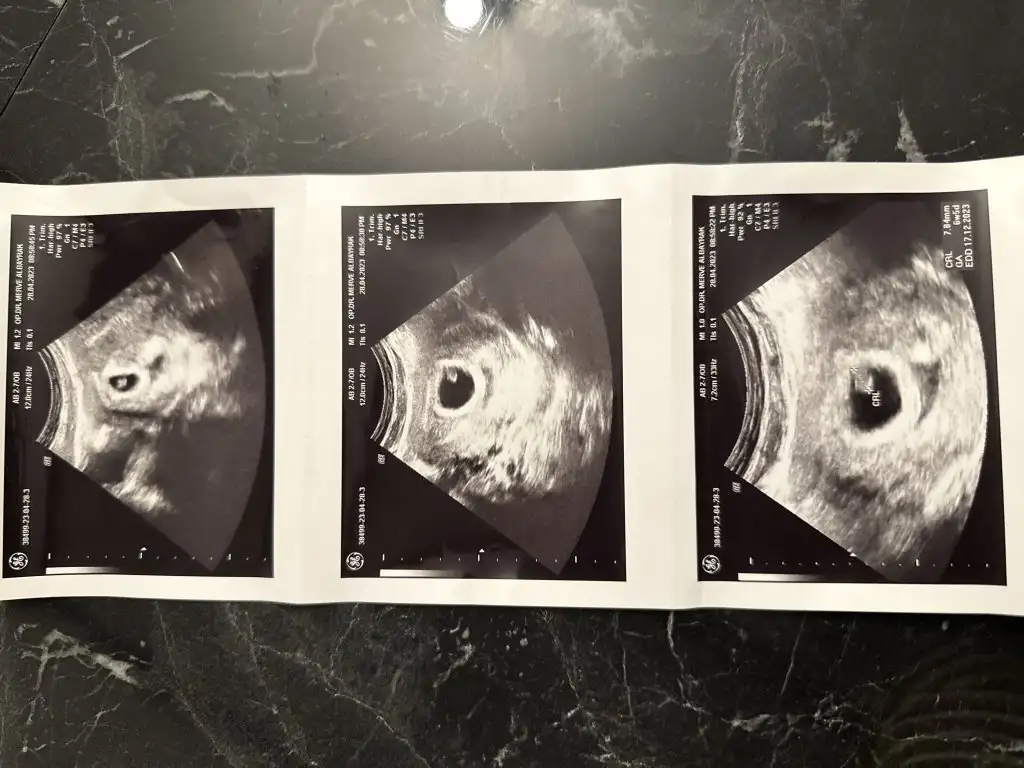

KizlarrrKızlar selam ben 6+4 oldum ama ultrasonda 5+4 çıktı bugün kese var dedi bebek var gibi dedi cuma günü özele gitsem kalp atışını duyarmiyim

Vajinal mi bakildi? Bebek daha embriyo oldugu icin vajinal daha rahat gorunuyor ve kalp atisi daha rahat duyuluyor bildigim kadariyla. Belki vajinal baktirsaniz daha net sonuc alirsinizKizlarrr